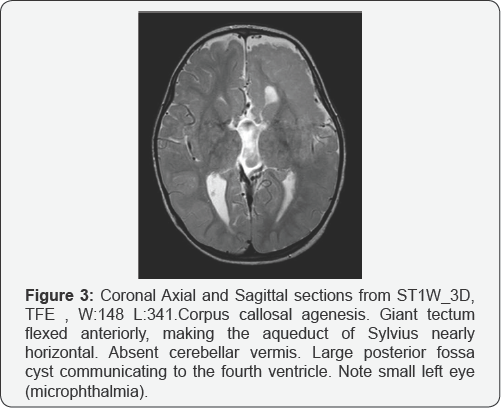

The patient had two MRI studies, at age of one month and age of 2 years. Both studies showed the same typical features of Delleman syndrome. He had polymicrogyria in the left frontal and parietal lobes (Figure 1a & 1b), Migrational anomalies in the form of heterotopic grey matter in the ependymal lining of left lateral ventricles, nodular heterotopias in the frontal and occipital lobes, more posteriorly (Figure 2a, 2b & 2c), and bands of heterotopic grey matter which were seen radiating from the periventricular area to the occipital cortex (Figure 3). The left lateral ventricle was slightly prominent. The above findings were confined to the left cerebral hemisphere. The right cerebral hemisphere was spared. Corpus callosum agenesis was also noted, without midline cyst or lipoma. The tectum was giant, slightly flexed anteriorly, making the aqueduct nearly horizontal. The vermis was absent and there was large posterior fossa cyst, communicating to the fourth ventricle (Figure 3). The left eye was small (microphthalmia) and there was a multiloculated cyst in the roof of left orbit anteriorly (Figure 4). The above findings are typical in a patient with the oculocerebrocutaneous syndrome [4-6].

The forebrain malformation includes frontal predominant polymicrogyria; periventricular nodular heterotopia; complete or partial agenesis of the corpus callosum, sometimes associated with interhemispheric cysts; and enlarged third and lateral ventricles, which can be complicated by hydrocephalus. The mid-hindbrain malformation consisted of a giant tectum, absent vermis, and large posterior fossa fluid collection. The midbrain tegmentum sometimes flexed forward, making the aqueduct nearly horizontal. The giant and dysplastic tectum was rotated upward well above the normal position and appeared to form an arch over the enlarged lower aqueduct in 7/8 patients. The cerebellar hemispheres were missing or hypoplastic with a dysplastic foliar pattern in 7/8 patients. The fourth ventricle communicated widely with a large posterior fossa fluid collection, sometimes associated with an occipital meningocele.